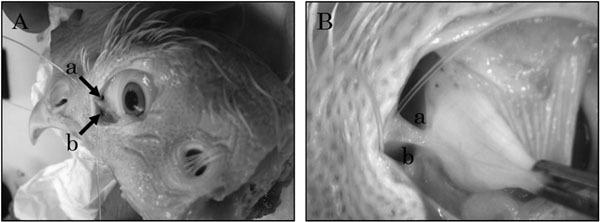

The nasal mucosa plays an important role in the immune system, with nasal mucous cells secreting mucin that, along with pili, exclude foreign substances from intervening. Nasal mucosal-associated lymphoid tissue (NALT), present in the nasal lamina propria, acts as a local immune system. In birds, the Harderian gland in the orbit also plays an important role in the local immune system. In this study, we analyzed the pathway from the nasolacrimal duct to the nasal cavity in chickens and the distribution of the nasal mucous cells responsible for defense mechanisms against pathogens. To determine the three-dimensional structure of the pathway from the nasolacrimal duct to the nasal cavity, we made casts of the anatomy by injecting an acrylic resin into the area. We then prepared paraffin sections to determine the distribution of the NALT and mucous cells. The mucous gland was clearly seen in the mucosal epithelium of the nasal cavity, suggesting that the pathway along the nasal cavity develops a nonspecific immune system to deal with large foreign substances, such as bacteria, using mucins that are secreted from the mucous glands. Hence, there is not only a physical barrier but also an antibacterial activity. Unlike in other animals, morphologically, the nasolacrimal duct in chicken becomes the ventral nasal meatus and opens into the choanae in the caudal portion of the nasal cavity. NALT was prominently present in the lamina propria of the ventral nasal meatus, suggesting the presence of a specific immune system protecting against avian viruses. Thus, responses to vaccine stimulation could be developed from tissues along the pathway of the ventral nasal meatus via the nasolacrimal duct running from the punctum. These morphological studies suggest that the instillation of eye drops could be used as an efficient vaccination method for avoiding respiratory diseases.